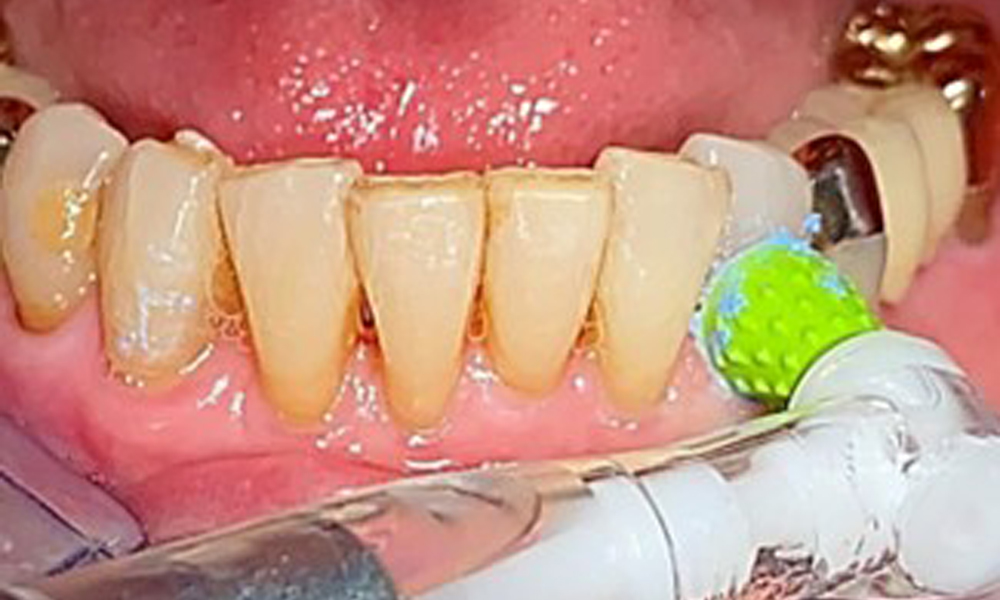

The dental findings are as follows: Combined removable implant and tooth-supported telescopic prostheses on implants 15, 13, 21, 23, 24, 25 and tooth 11 (Fig. 1, Fig. 2, Fig. 3). The patient was fitted with a fixed mandibular denture. Adequate bridges were present over 37 to 34 and 45 to 47 (Fig. 4), the crown margins were intact and there were no active caries. A composite filling with a marginal gap was present on tooth 43. There was mandibular gingival recession, exposing 1 to 3 mm of root surface. This also applies to 11.

An air polishing system should be used with low-abrasive powder to remove biofilm from the restoration margins, interdental areas and implant surfaces (Fig. 12). Selective polishing (Fig. 13) should be used to smooth any less sensitive areas, as this decreases bacterial reattachment (9).

Interdental cleaning with brushes (Fig. 9) or dental floss is just as important as cleaning the tongue.